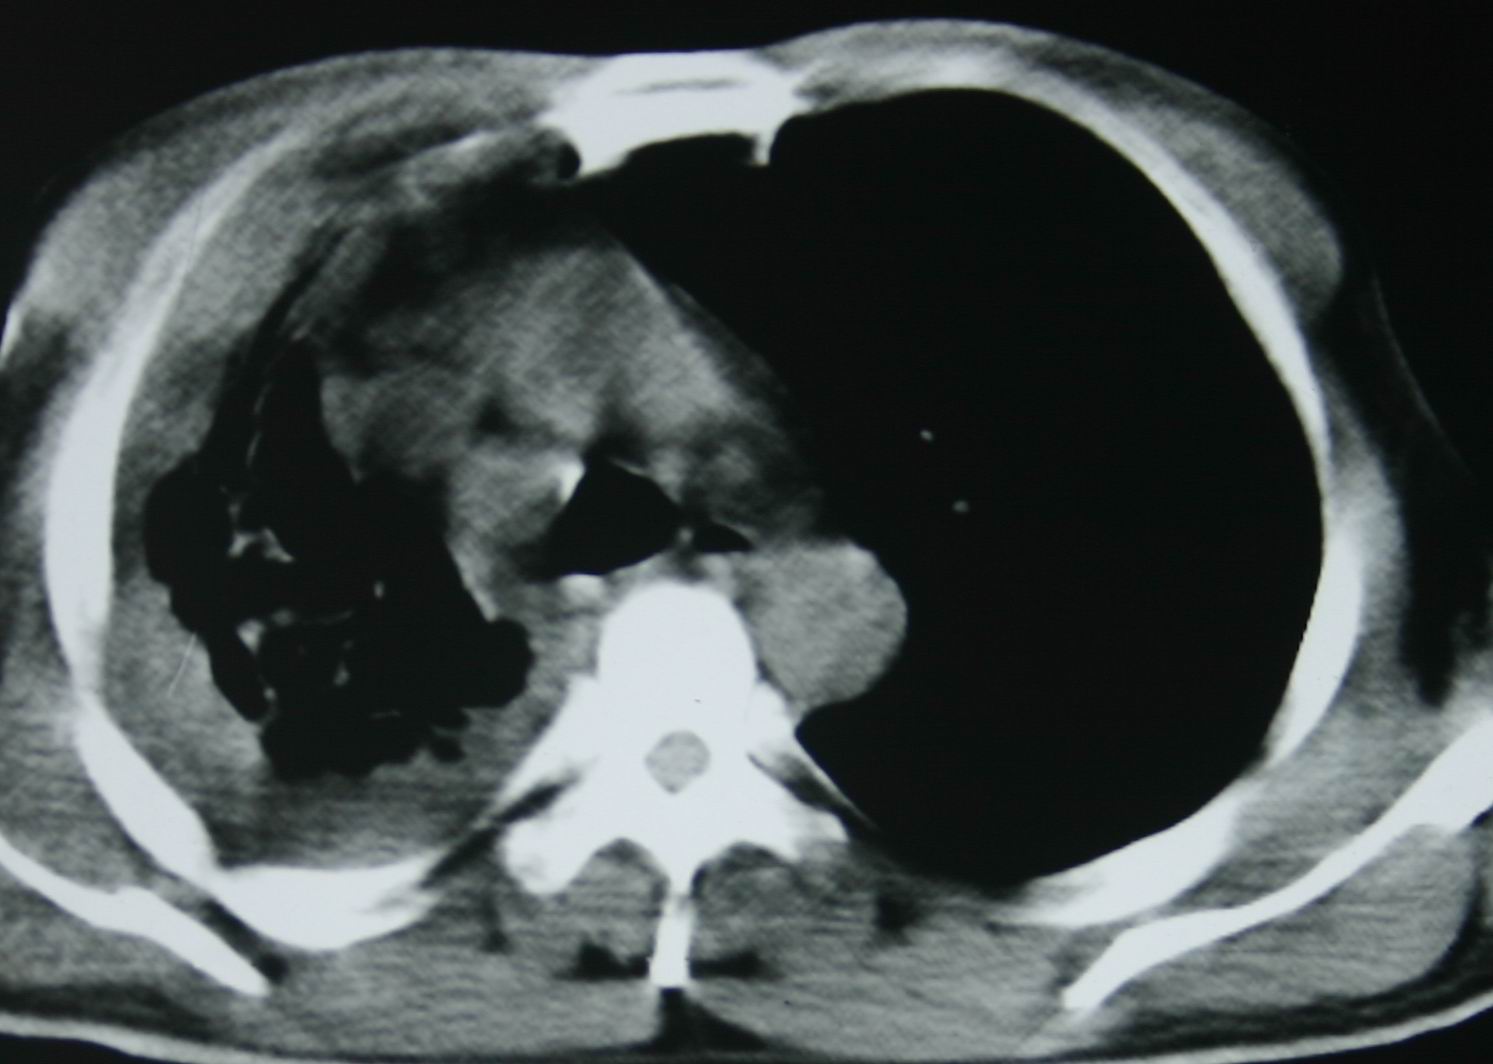

患者,男 ,48岁,反复咯血三个月,每三到五天咯一次,每次约200ml,鲜红色,无明显咳痰,咳嗽明显,无明显胸痛,无发烧,初期以抗感染、止血治疗,第一次ct报占位,支气管镜未见明显ca细,肺ca标志物、tb抗体均阴性,经过垂体后叶素、酚妥拉明、头胞他定、洛美沙星、立止血等治疗后,现病人一般情况好,停止咯血10天,咳嗽减少,咳黄脓痰,每日一次,每次30ml。现复查ct

右肺膨胀不全,纵隔右侧移位。肺内有感染,胸腔有积液。建议老片对比。

1)考虑右肺继发性肺结核合并感染。2)右侧胸腔积液+胸膜增厚。

支持:右肺膨胀不全,纵隔右侧移位。肺内有感染,胸腔有积液。建议老片对比。